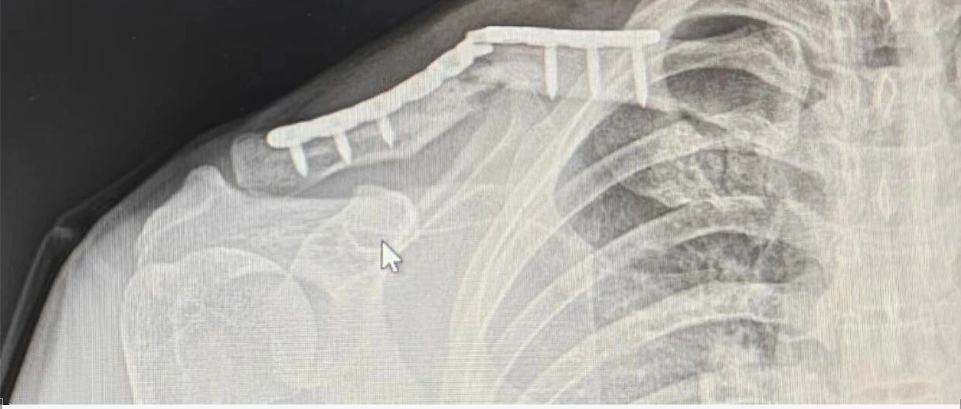

肩关节镜技术

117分钟

5.5万人学习

肩关节镜手术演示

123分钟

3.5万人学习